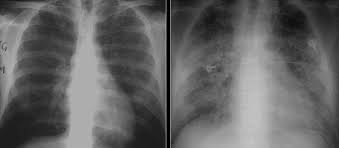

“폐에 물이 찼다”는 말을 들으면 대부분 같은 그림을 떠올리지만, 실제로는 두 가지가 섞여 불리는 경우가 많습니다. 하나는 폐 안(폐포)에 물이 스며드는 폐부종, 다른 하나는 폐 바깥(흉막 사이)에 물이 고이는 흉수(흉막삼출)예요. 둘 다 숨이 차지만, 동반 증상과 위험 신호가 조금 다릅니다. 오늘은 “폐에 물이 차는 증상”을 최대한 쉽게, 실제로 느끼는 증상 중심으로 정리해드릴게요.

폐부종(폐 안에 물)일 때 특징적인 신호

폐부종은 말 그대로 폐포 쪽으로 물이 스며들어 산소 교환이 어려워지는 상태라, 증상이 갑자기 세게 올 수 있습니다. 특히 아래 느낌이 있으면 “그냥 감기인가?”로 넘기기 어렵습니다.